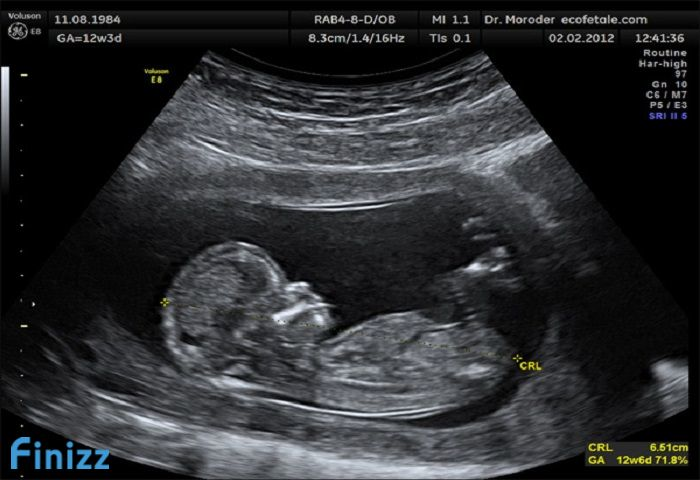

• Xác định tuổi thai nhi, theo dõi quá trình phát triển của thai nhi

Loại hình siêu âm

– Siêu âm 2D: đây là hình thức siêu âm cơ bản, thường được thực hiện với mục đích chẩn đoán có thai hay không, xác định thai bao nhiêu phôi, kiểm tra vị trí của thai nhi, cũng như phát hiện các dị tật bẩm sinh ở thai nhi. Siêu âm 2D thường được thực hiện khi thai ở 18 đến 20 tuần tuổi và có phí siêu âm thai rẻ nhất trong 3 loại.

– Siêu âm 3D: Là loại siêu âm 3 chiều cho hình ảnh màu, áp dụng với các thai nhi lớn và có thể nhìn thấy hình hài của bé. Ngoài ra, bác sĩ còn phát hiện ra các dị tật cũng như biết được chính xác tuổi, giới tính của thai nhi.

– Siêu âm 4D: được xây dựng trên cơ sở công nghệ quét 3D, cho hình ảnh 3D động. Thông qua hình thức siêu âm này, các mẹ có thể nhìn thấy những cử chỉ của con, thậm chí có thể lưu lại trong DVD để làm kỷ niệm. Loại hình này được dùng cho các thai có độ tuổi lớn, thường là vào 3 tháng cuối của thai kỳ. Phí siêu âm thai 4D là đắt nhất.